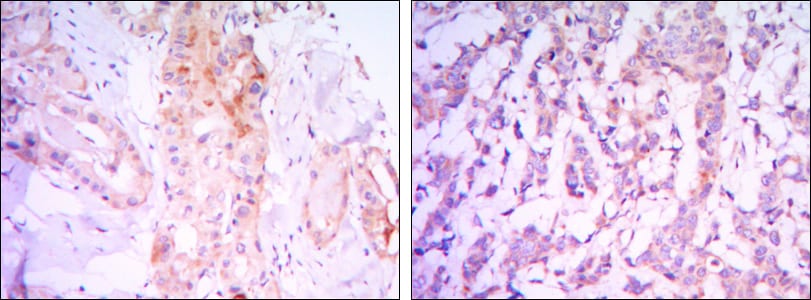

Immunohistochemical analysis of paraffin-embedded human thyroid gland tissues (left) and human breast carcinoma (right) using RICTOR mouse mAb with DAB staining.